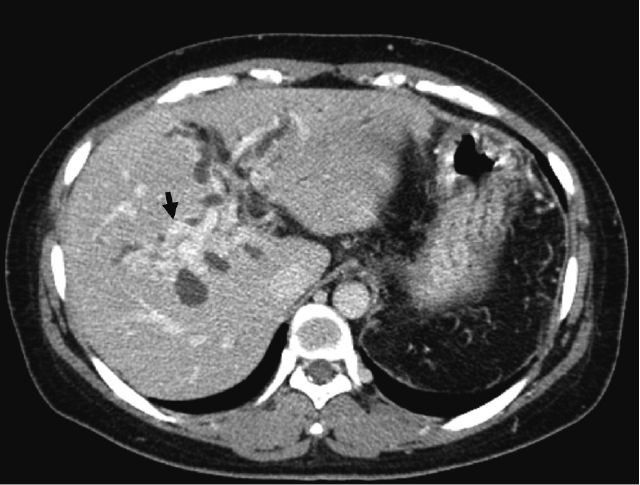

腹部造影CT検査:門脈本幹は描出されず,肝門部で海綿状に側副血行路の発達を認めた.両側肝内胆管の拡張も認め,膵内胆管周囲では胆管静脈瘤は著明に発達していた(Figure 1).

症例1:胆管静脈瘤による閉塞性黄疸発症時の造影CT検査所見(門脈相水平断).膵内胆管周囲で胆管静脈瘤は著明に発達している(矢印).